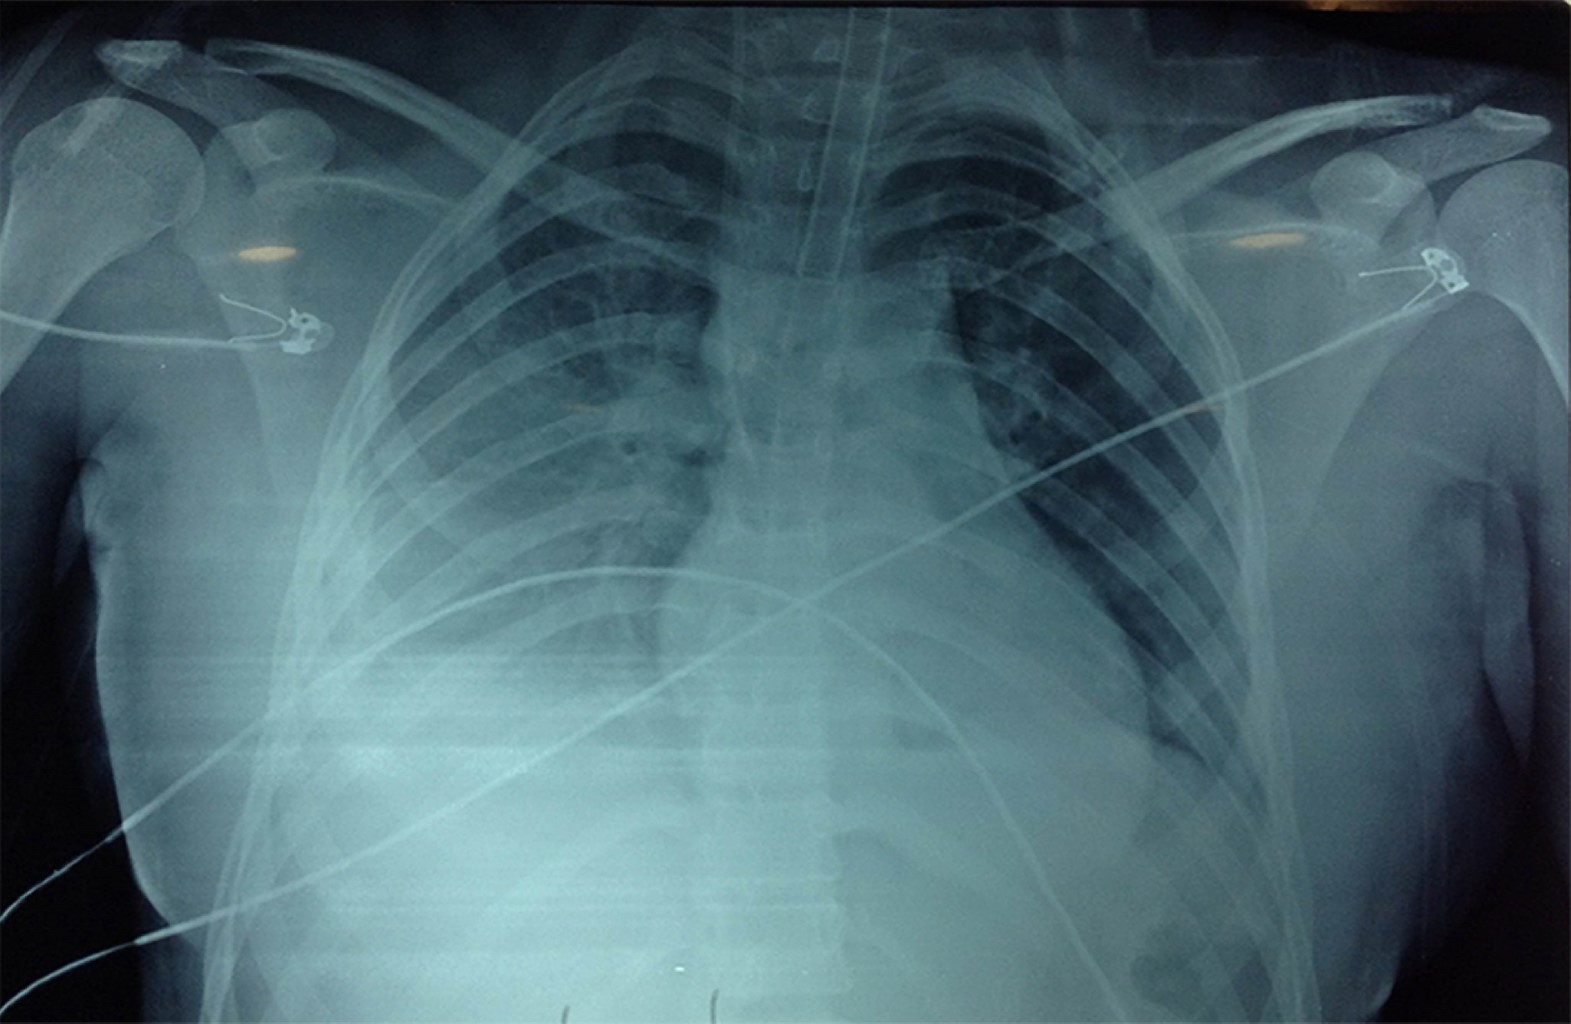

Mujer de 17 años de edad sin antecedentes de importancia, la cual ingresa al área de urgencias trasladada por paramédicos en camilla después de sufrir trauma debido a desaceleración súbita por caída de 10 metros de altura, sufriendo contusión directa y múltiples fracturas en miembros pélvicos, pelvis y cara, por lo que se le realizó colocación de fijadores externos en pelvis y lavado quirúrgico. Ingresó a terapia intensiva con Glasgow de 15 puntos, facies álgica, palidez de piel y tegumentos, con dolor intenso en pelvis escala visual analógica (EVA) 9/10. Con requerimiento de oxígeno suplementario a cinco litros por minuto con disminución de los movimientos de amplexión y amplexación del hemitórax derecho, matidez a la percusión, aumento de las vibraciones vocales y disminución de murmullo vesicular en región basal de hemitórax derecho; signos vitales: presión arterial (TA) 90/50 mmHg, frecuencia cardiaca (FC) 109 latidos por minuto (lpm), frecuencia respiratoria (FR) 16 respiraciones por minuto (rpm), saturación periférica de oxígeno (SpO2) 100%, temperatura 36.6°C, llenado capilar 4 s. Laboratorio: hemoglobina (Hb) 6.8 g/dL, hematocrito (Hct) 19.9%, plaquetas 88,000 × 109/L, tiempo de protrombina (TP) 17.3 s, tiempo parcial de tromboplastina (TPT) 27.5 s, índice internacional normalizado (INR) 1.29, creatina fosfocinasa (CPK) 1,282.52 U/L, isoenzima MB de la creatina cinasa (CPK-MB) 1.2 ng/dL. Se realiza tomografía de abdomen, la cual evidencia hematoma retroperitoneal evolutivo desde plano fascial y perirrenal posterior. La paciente ameritó ventilación mecánica y fue sometida a laparotomía exploradora de urgencia. A su egreso de quirófano y posterior a la reanimación con hemoderivados, continuó con datos de choque con TA 60/40 mmHg, frecuencia cardiaca 105 lpm, llenado capilar 5 s, por lo cual requirió manejo con doble vasopresor: norepinefrina 0.15 μg/kg/min y vasopresina 0.03 UI/h; sin embargo, continua con presión arterial media < 65 mmHg. Se le realiza radiografía de tórax (Figura 1) donde se observa contusión pulmonar en región basal de hemitórax derecho, con corazón en gota. Electrocardiograma (ECG) (Figura 2): ritmo sinusal, frecuencia cardiaca 120 lpm, con aplanamiento de la onda T en la mayoría de las derivaciones excepto en V2, depresión del segmento ST en aVR y ausencia de elevación del segmento ST en V1. Se realizó ecocardiograma transtorácico (ECOTT) (Figuras 3 y 4), en el que se observa movilidad conservada solamente en ápex, condicionando tracción del ventrículo derecho; resto con hipocinesia generalizada, ventrículo derecho dilatado con función sistólica global deprimida con hipocinesia generalizada, fracción de eyección del ventrículo izquierdo (FEVI) 21.7%, puntaje InterTAK de 49 puntos. Requirió manejo con inotrópico dobutamina 3 μg/kg/min con mejoría de presión arterial media y datos de choque. Presentó una evolución favorable, logrando retiro de inotrópico 24 horas después por mejoría con control ecocardiográfico seis días después (Figura 5), con recuperación de FEVI: 64.3%. La paciente requirió fijación de fracturas de huesos de la cara y miembros pélvicos y posteriormente fue trasladada a otra unidad hospitalaria para continuar con tratamiento ortopédico.

Figura 1